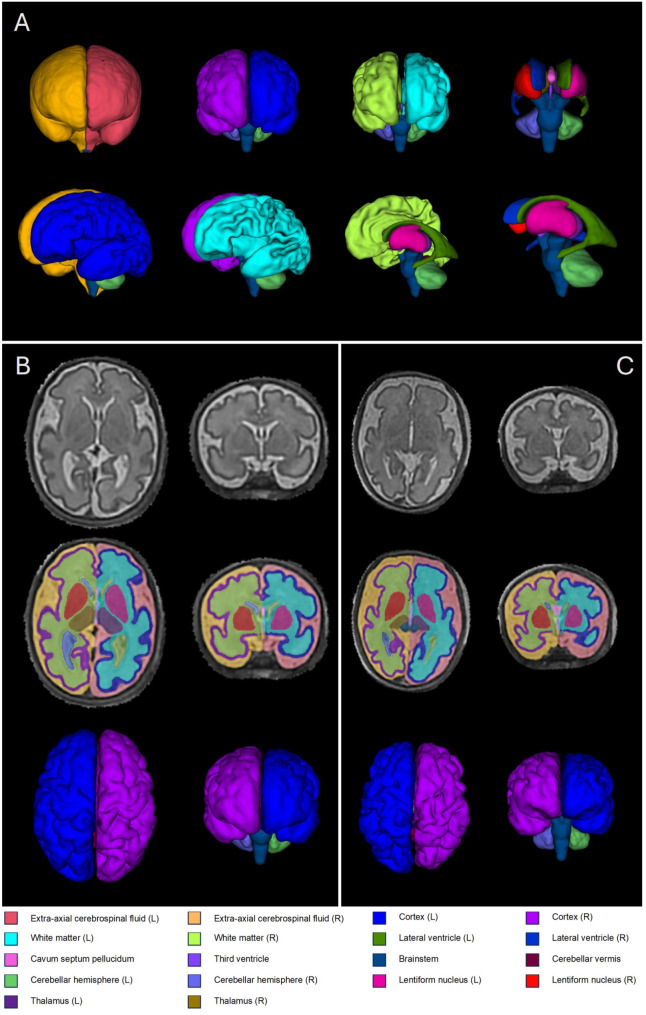

Methods: In this small, exploratory study, we use fetal MRI to assess volumetric brain development in 22qDS by comparing fetal brain morphometry to a set of gestation and sex-matched healthy controls, and a cohort of gestation and sex-matched fetuses with the same CHD diagnoses but without 22q11.2 deletion. Structural T2-weighted fetal brain images were acquired using a 1.5T MRI scanner. MR scanner and sequence parameters were identical in all cohorts. Motion-corrected images underwent segmentation using an automated pipeline developed for fetal brain MRI. Total brain tissue volumes, volumes for four different tissue regions (cortical grey matter, white matter, deep grey matter and cerebellum), cerebrospinal fluid and total intracranial volumes were calculated.